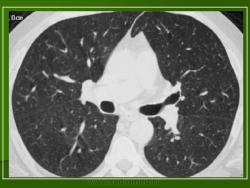

Изучение скелетограмм у 27 из 29 больных позволило выявить изменения, подтвердившие диагноз данного заболевания. Это указывает на высокую диагностическую ценность рентгенологического обследования при ГКЛ. Наиболее часто определялись поражения черепа в виде множественных (24) или единичных (3) дефектов в костях свода, где четко прослеживалась «штампованность» очагов. Дефекты не содержали секвестров, имели различную форму, величину, четкие наружные и неровные, фестончатые внутренние контуры. Периостальная реакция отсутствовала. При множественных участках деструкций картина напоминала «географический или ландкартообразный» череп, или «изъеденную молью ткань» (Рис.1).

В 5 наблюдениях (21%) из больных с распространенной формой заболевания отмечались изменения в легких в виде обогащения, избыточности легочного рисунка, его деформации по сетчато-петлистому типу, очаговых теней. Корневая и медиастинальная аденопатия отсутствовали. В 1 случае в легких выявлена киста, которая периодически осложнялась нагноением (Рис. 4).

Поражение легочной ткани (рис. 22) свойственно любому возрасту. Часто больные имеют общие симптомы — лихорадку, слабость, реже — кашель, одышку, боли в грудной клетке. На рентгенограммах отмечается деформация и усиление легочного рисунка и микроузловые инфильтративные тени. Поражение костного мозга (с наличием клеток Лангерганса) сопровождается цитопенией периферической крови.

Рис. 22. Поражение легких при Лангер-гансово-клеточном гистиоцитозе.